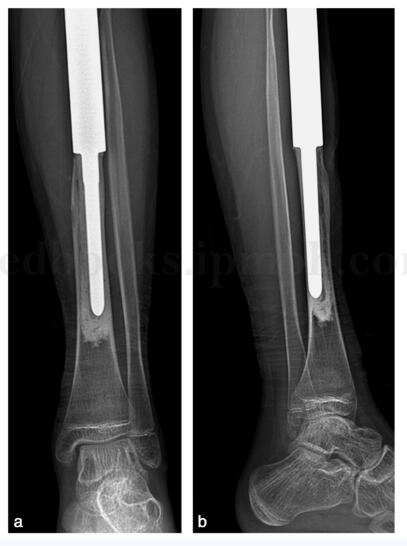

完善术前准备后,在连续硬膜外麻醉下行胫骨近端瘤段切除临时假体重建术(图47‐6)。患者平卧位,在止血带下操作。手术采用胫骨近端前内侧入路。梭形切除活检道。向两侧游离,注意保护窝血管神经束及腓总神经,显露胫骨近端,切断髌腱,切开关节囊,距止点1cm切断交叉韧带及内外侧副韧带,距关节面15cm截断胫骨。冲洗松止血带止血后安装胫骨侧的临时假体,远端髓内针以骨水泥固定。以不可吸收线把前后交叉韧带及侧副韧带断端固定到临时假体的聚乙烯衬垫,把髌腱残端与鹅足及深筋膜缝合固定。放置引流,冲洗后关闭伤口。术后以长腿石膏后托固定于膝关节伸直踝关节中立位。术毕常规应用抗生素7~10天,24小时引流小于25ml 后拔出引流管。

图47‐6 术后胫骨正侧位片示胫骨近端人工关节重建术后,膝关节无脱位a﹒正位片;b﹒侧位片

:患者术后未见明显并发症。目前患者术后5年,未发现局部复发及远隔转移。患者跛行步态。左膝关节主动活动度(伸直至屈曲):0~90°。下肢长度测量显示左胫骨较右胫骨短缩4.4cm,左股骨较右股骨短缩约3.1cm(图47‐7)。X 线显示假体未见明显松动,膝关节无脱位(图47‐8~图47‐10)。患者站立时由骨盆及脊柱倾斜来调整肢体长度(图47‐11)。

图47‐10 术后5年X 线显示假体未见明显松动,膝关节位置无脱位a﹒正位片;b﹒侧位片